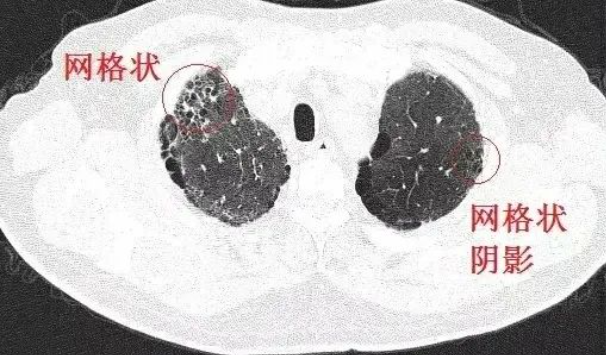

間質性肺病是指許多急性和慢性肺實質病變引起肺泡壁和肺泡腔不同程度的炎癥和纖維滲出,導致彌漫性肺間質纖維化發展的一組疾病。其病理變化可嚴重影響肺泡上皮細胞和毛細血管內皮細胞的功能和氣體交換,導致疾病晚期呼吸衰竭。

日常生活中最常見的間質性肺病包括各種職業性肺病,如肺塵埃沉著病、石棉肺和矽肺。 2019 年,中國科學院學者證實,人體內存在一種參與肺再生的肺多能干細胞。它可以根據需要“分化”,在肺部完成“跨界維持”,為肺部疾病的干細胞治療提供堅實的理論基礎。